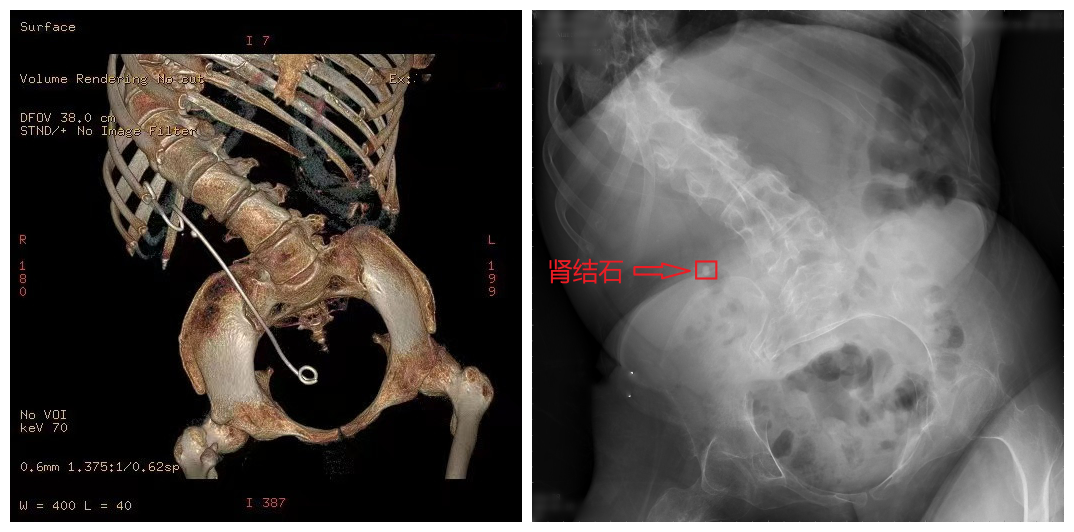

清华长庚泌尿外科为身体畸形患者除结石 终止其四年之痛